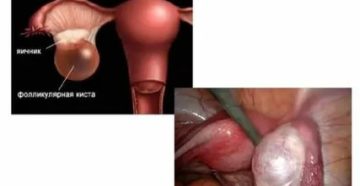

Сколько может не рассасываться фолликулярная киста яичника Фолликулярная киста яичника является ретенционным образованием половой железы…